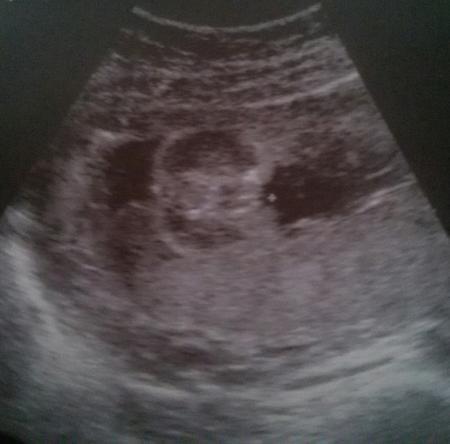

Hallo ihr mit schwangeren Ein hundert prozentiges outing wollte der Doc nicht geben. Er meinte Tendenz zum Mädchen. Was meint ihr ?

Ich würde auch zum Mädchen tendieren.

Ich würde auch mädchen sagen :)

Hi. Ich habe selbst 2 Mädels und würde auch sagen - a Mädle! . LG

So sah es bei mir auch aus, als die Ärztin meinte sie sei sehr sicher, dass es n Mädchen wird. Noch is sie nicht da, aber ich trau so Ärzten dahingehend mal :)

Mein Mädchen sieht auch so aus und ich vertrau der FA. Sie hat sehr lange gewartet, bis sie es ausgesprochen hat, weil sie sich sicher sein wollte. War jetzt als sie es sagte schon in der 27. Woche